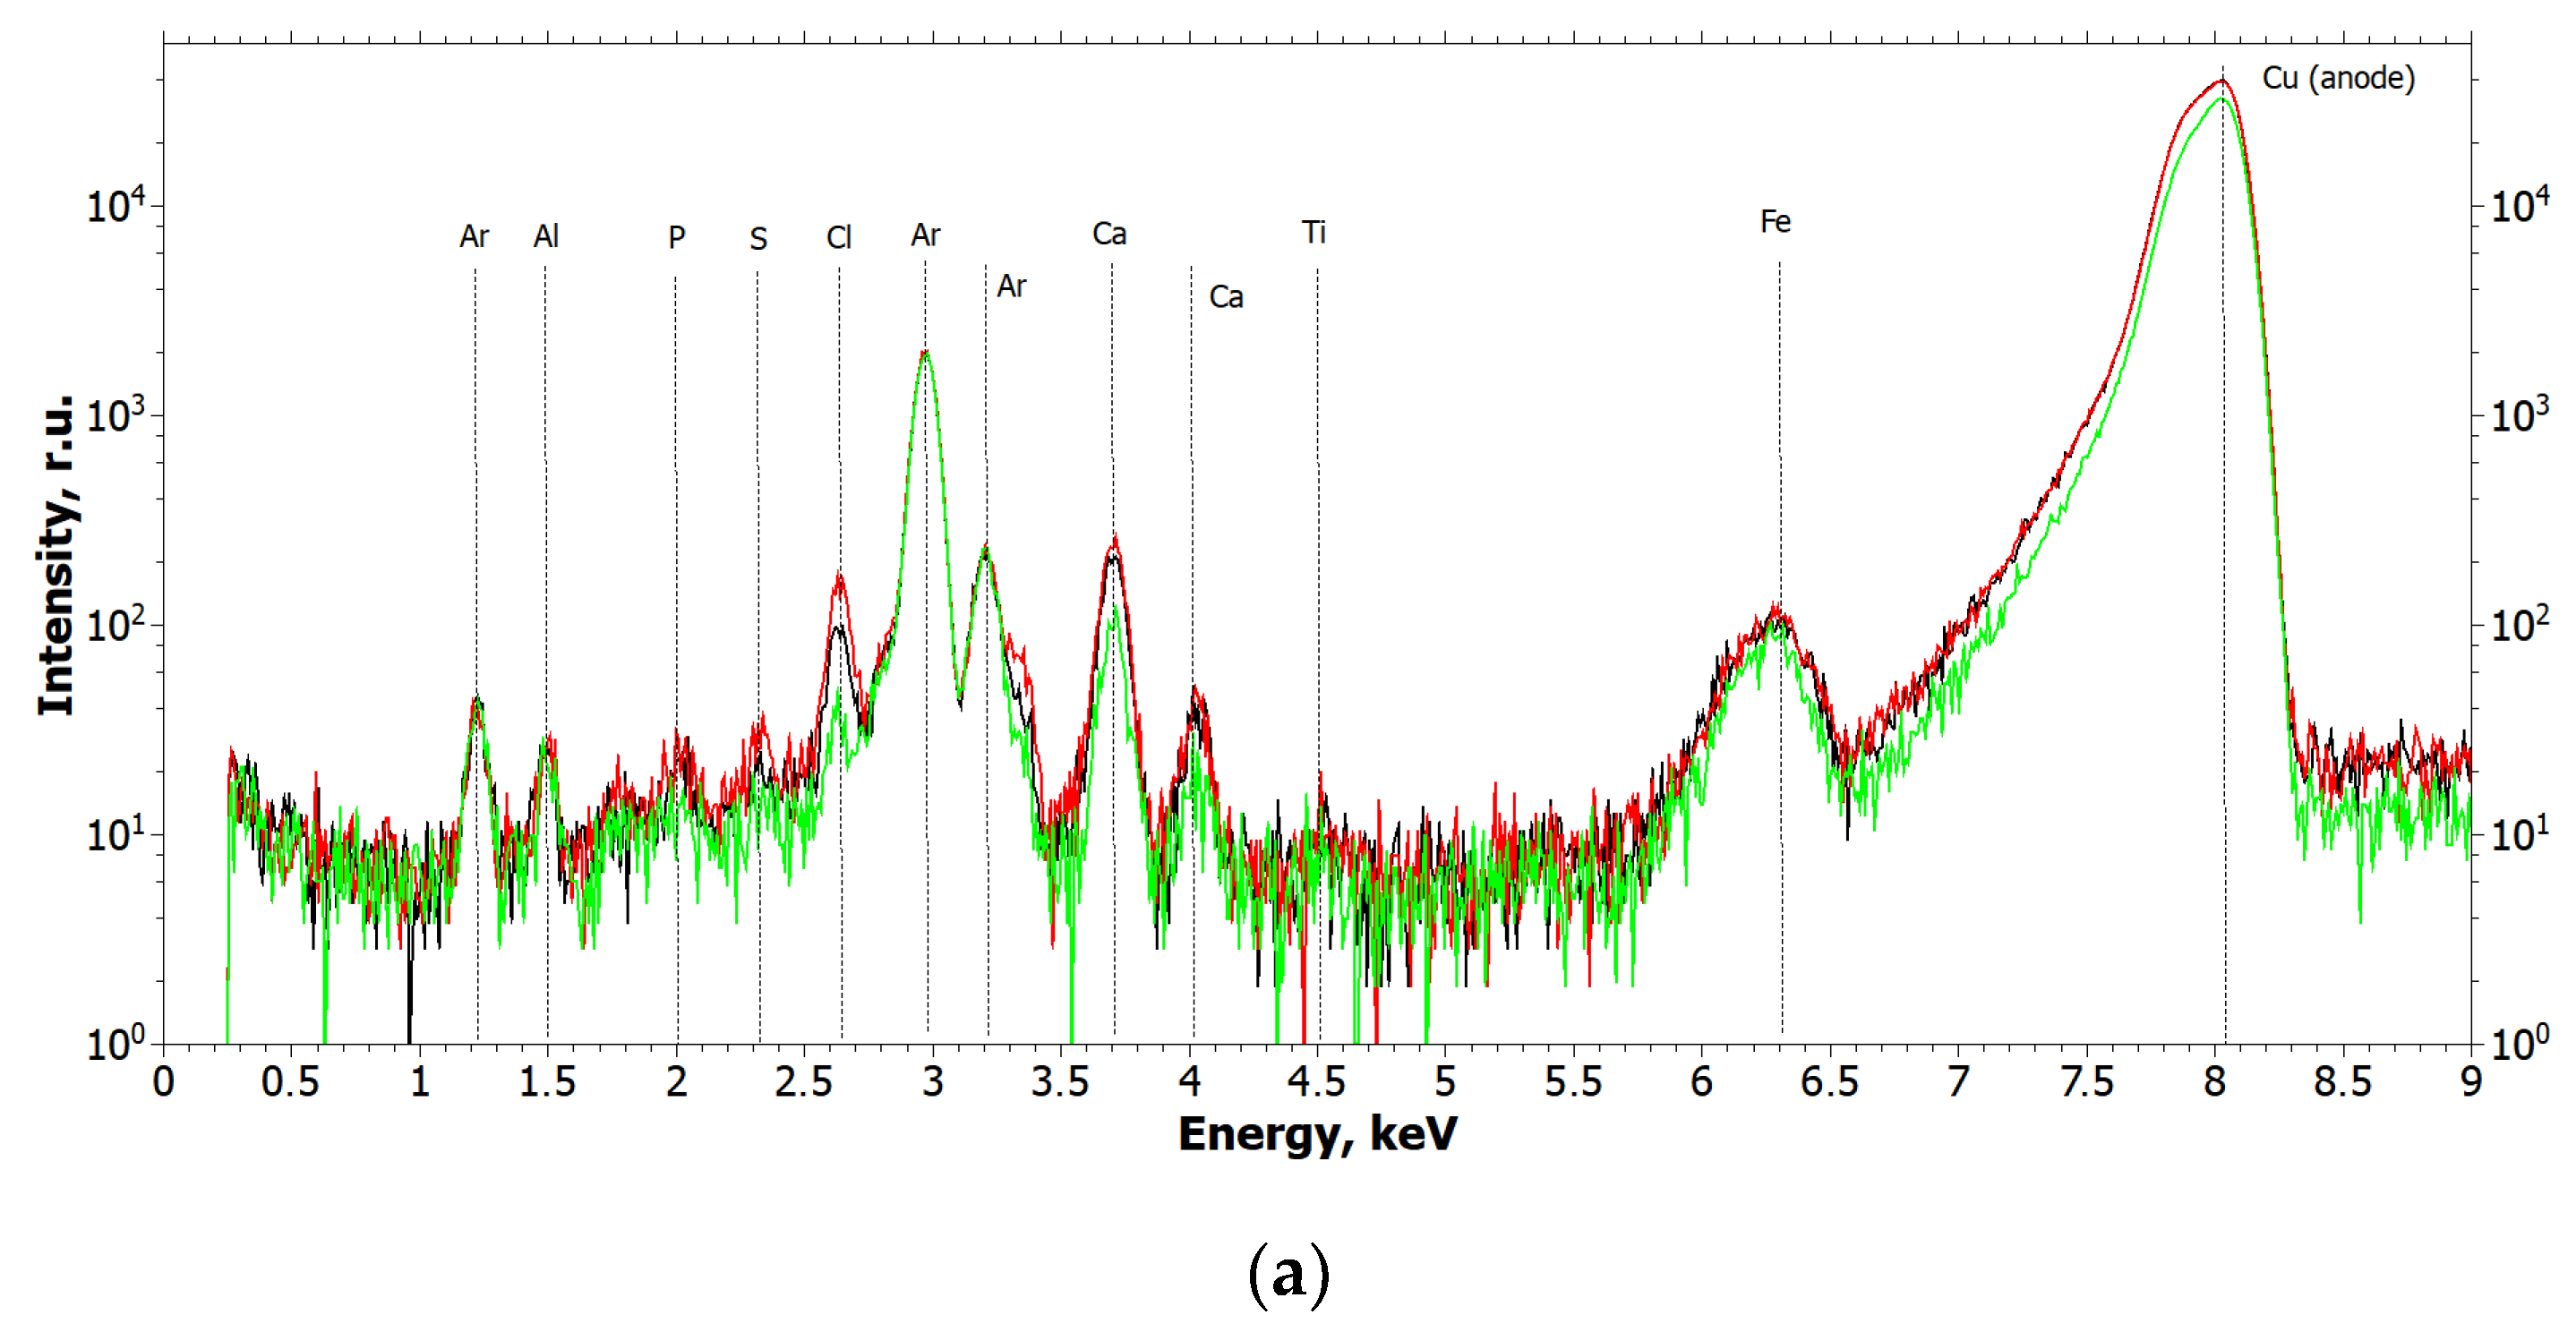

2.1.1. Results of X-ray and Electron Microscopic Studies

4.3. X-ray Fluorescence Analysis (XRF)

- Cu tube (focus size 12×2.0 mm), 40 kV × 40 mA mode;

- Monochromator—silicon (symmetrical), reflection (111);

- Wavelength—1.54 Å (E = 8.047 keV);

- Beam size—10.0×1.0 mm (slits adjustable);

- Detector—Amptek 123SDD (Amptek, Bedford, MA, USA);

- Exposure—1200 s per measurement.

- Ag tube (focus size 10 × 1.0 mm), 40 kV × 40 mA mode;

- Monochromator—silicon (symmetrical), reflection (111);

- Wavelength—0.55 Å (E = 22.162 keV);

- Beam size—10.0 × 1.0 mm (slits adjustable);

- Detector—Amptek 123SDD (Amptek, Bedford, MA, USA);

- Exposure—1200 s per measurement.